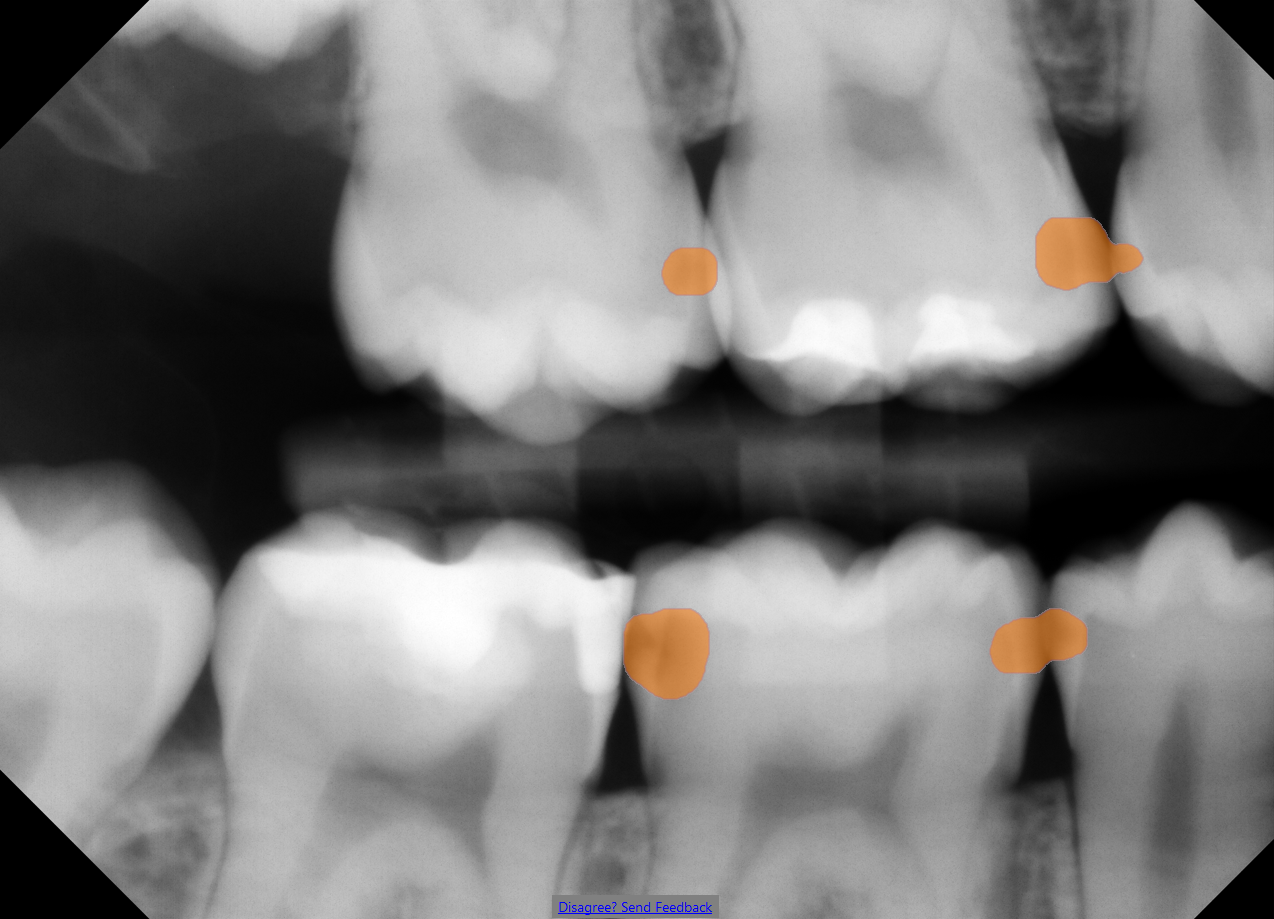

3. Get Instant Clarity

Color-coded highlights show what may need a second look.

Green/yellow/red color display has not received FDA clearance.